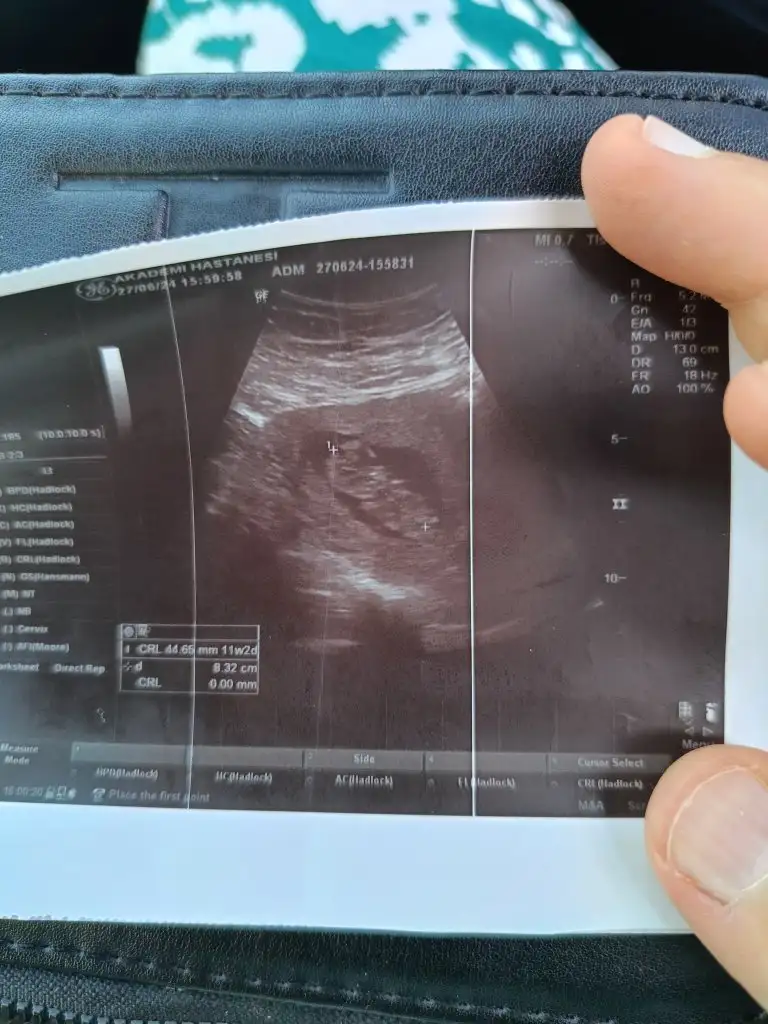

Kızlar selamlar bugün kontrole gittim 1 haftadır üst solunum yolu enfeksiyonu geçiriyordum hiç iyi değildim ama bebişi görünce biraz moralim düzeldi cinsiyetle ilgili hiç yorum yapmadı anlayan çıkar mı aranızda ayrıca haftaya ikili test için çağırdı bizde durumlar böyle 🧡 umarım hepiniz iyisinizdir

Burnuna baktı her şey yolunda dedi ense kalınlığı da 0,90 çıktı . Cinsiyet için de tahminde bulundu erkeğe benziyor ama değişebilir kesin değil dedi .

Eklentiler

• 411E9440-D745-41AA-8F1E-3BE38BCC9F43.webp

411E9440-D745-41AA-8F1E-3BE38BCC9F43.webp

27,6 KB · Görüntüleme: 70